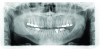

Panoramic radiograph from 2009.

Figure 6

Panoramic radiograph taken in 2017. Note increased occlusal erosion of tooth No. 18.

Figure 7

Periodontal: The periodontal examination revealed generalized clinical attachment loss but no pockets greater than 3 mm, no bleeding on probing, and no significant mobilities of any teeth. Adequate attached gingiva was present on all teeth. Home care was acceptable. Generalized tissue and bone loss was evident on the buccal surfaces of the posterior teeth. His periodontal disease was classified as stage II, generalized, grade A based on the radiographic

bone loss of more than 2 mm but less than 4 mm interdentally and the comparisons of

interdental bone level from his two panographic radiographs taken 8 years apart.

Biomechanical: Significant tooth structure loss had occurred between 2009 and 2017 (Figure 1 through Figure 3). Severe attrition had occurred on the anterior teeth, especially tooth No. 11. Severe erosion and abrasion were present on teeth Nos. 11, 18, 20, 21, 28, 29, 31, and 32 (Fig-

ure 4). The patient had generalized sensitivity, and tooth No. 18 was painful due to deep erosion, which approached the pulp chamber. Teeth Nos. 7 and 10 had moved out of position and rotated (Figure 5). The progression of erosion over the 8-year period could also be seen radiographically and was especially noticeable on tooth